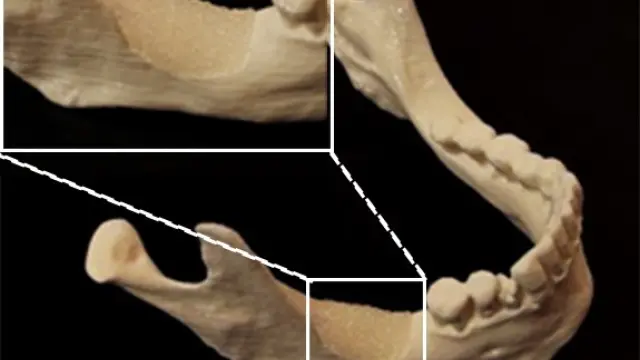

Dichos implantes han sido evaluados in vitro e in vivo en el Instituto Nacional Francés para la Investigación Médica en Estrasburgo, en el grupo de Nadia Jessel, demostrándose en modelos animales que dichos implantes favorecen la regeneración dental y que los dientes regenerados están vascularizados e inervados, dos características necesarias para obtener una buena regeneración.